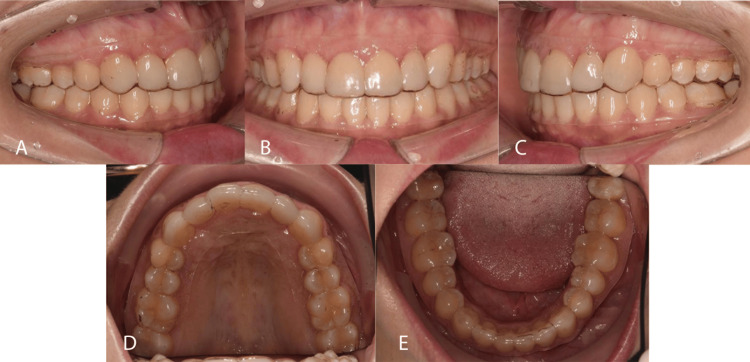

Figure 9. Post-treatment intra-oral photographs.

A: Right lateral view; B: Frontal view; C: Left lateral view; D: Upper occlusal view; E: Lower occlusal view

Figure 10. One-year post-treatment with vacuum-formed retainers.

Post-treatment, ideal Class I occlusion was achieved bilaterally with a functionally stable cusp-embrasure relationship. Nevertheless, a significant deep bite of around 50% persisted, potentially because of the extended length of the veneer. Additional palatal root torque should be applied to the upper left canine to ensure optimal final positioning. However, the patient expressed satisfaction with the outcomes. The outcomes obtained remained stable one year after the treatment.